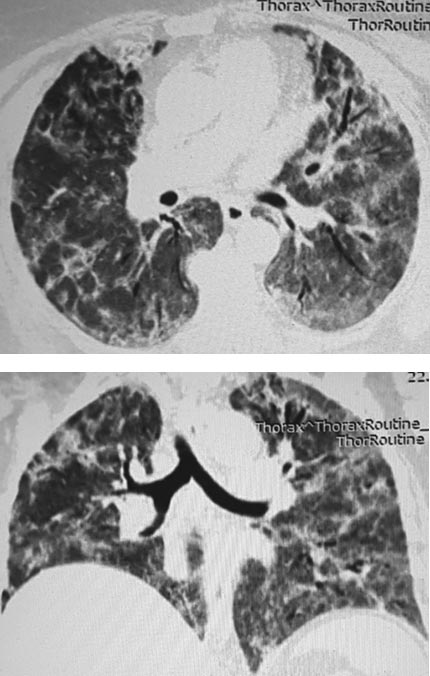

К 5-му дню госпитализации состояние не улучшалось. В связи с отягощением респираторного статуса пациентка была переведена на высокопоточную оксигенацию, прогрессировала лимфопения, нарастал уровень маркёров воспаления (С-реактивного белка до 171 мг/л, ферритина до 402 мкг/л), температура тела была нормальной. По данным контрольной РКТ зарегистрировано значимое нарастание объёмов поражения с расширением полей «матового стекла» и появлением участков консолидации лёгочной ткани (рис. 2).

Рис. 2. Рентгеновская компьютерная томограмма на день телемедицинского консилиума (КТ 3)

Состояние было расценено как цитокиновый шторм с клиническими проявлениями в виде ОРДС. Решением телемедицинского консилиума была дополнительно назначена однократная инфузия антицитокинового препарата (ингибитора интерлейкина-6) олокизумаба. Был получен ответ в виде значимого снижения активности воспалительных маркёров. При этом, несмотря на усиление режимов антикоагулянтной терапии (гепарин 1800 ЕД/ч), сохранялись явления тяжёлой дыхательной недостаточности.